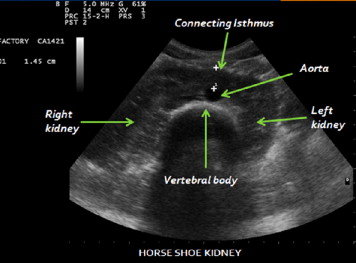

12. kép:

Patkóvese

Ezen a képen egy fejlődési variáció látható. Ez a patkóvese. A képen jól látható a jobb és a bal vese és az azokat összekötő parenchyma híd ami a gerinc és a hasi főverőér előtt helyezkedik el.